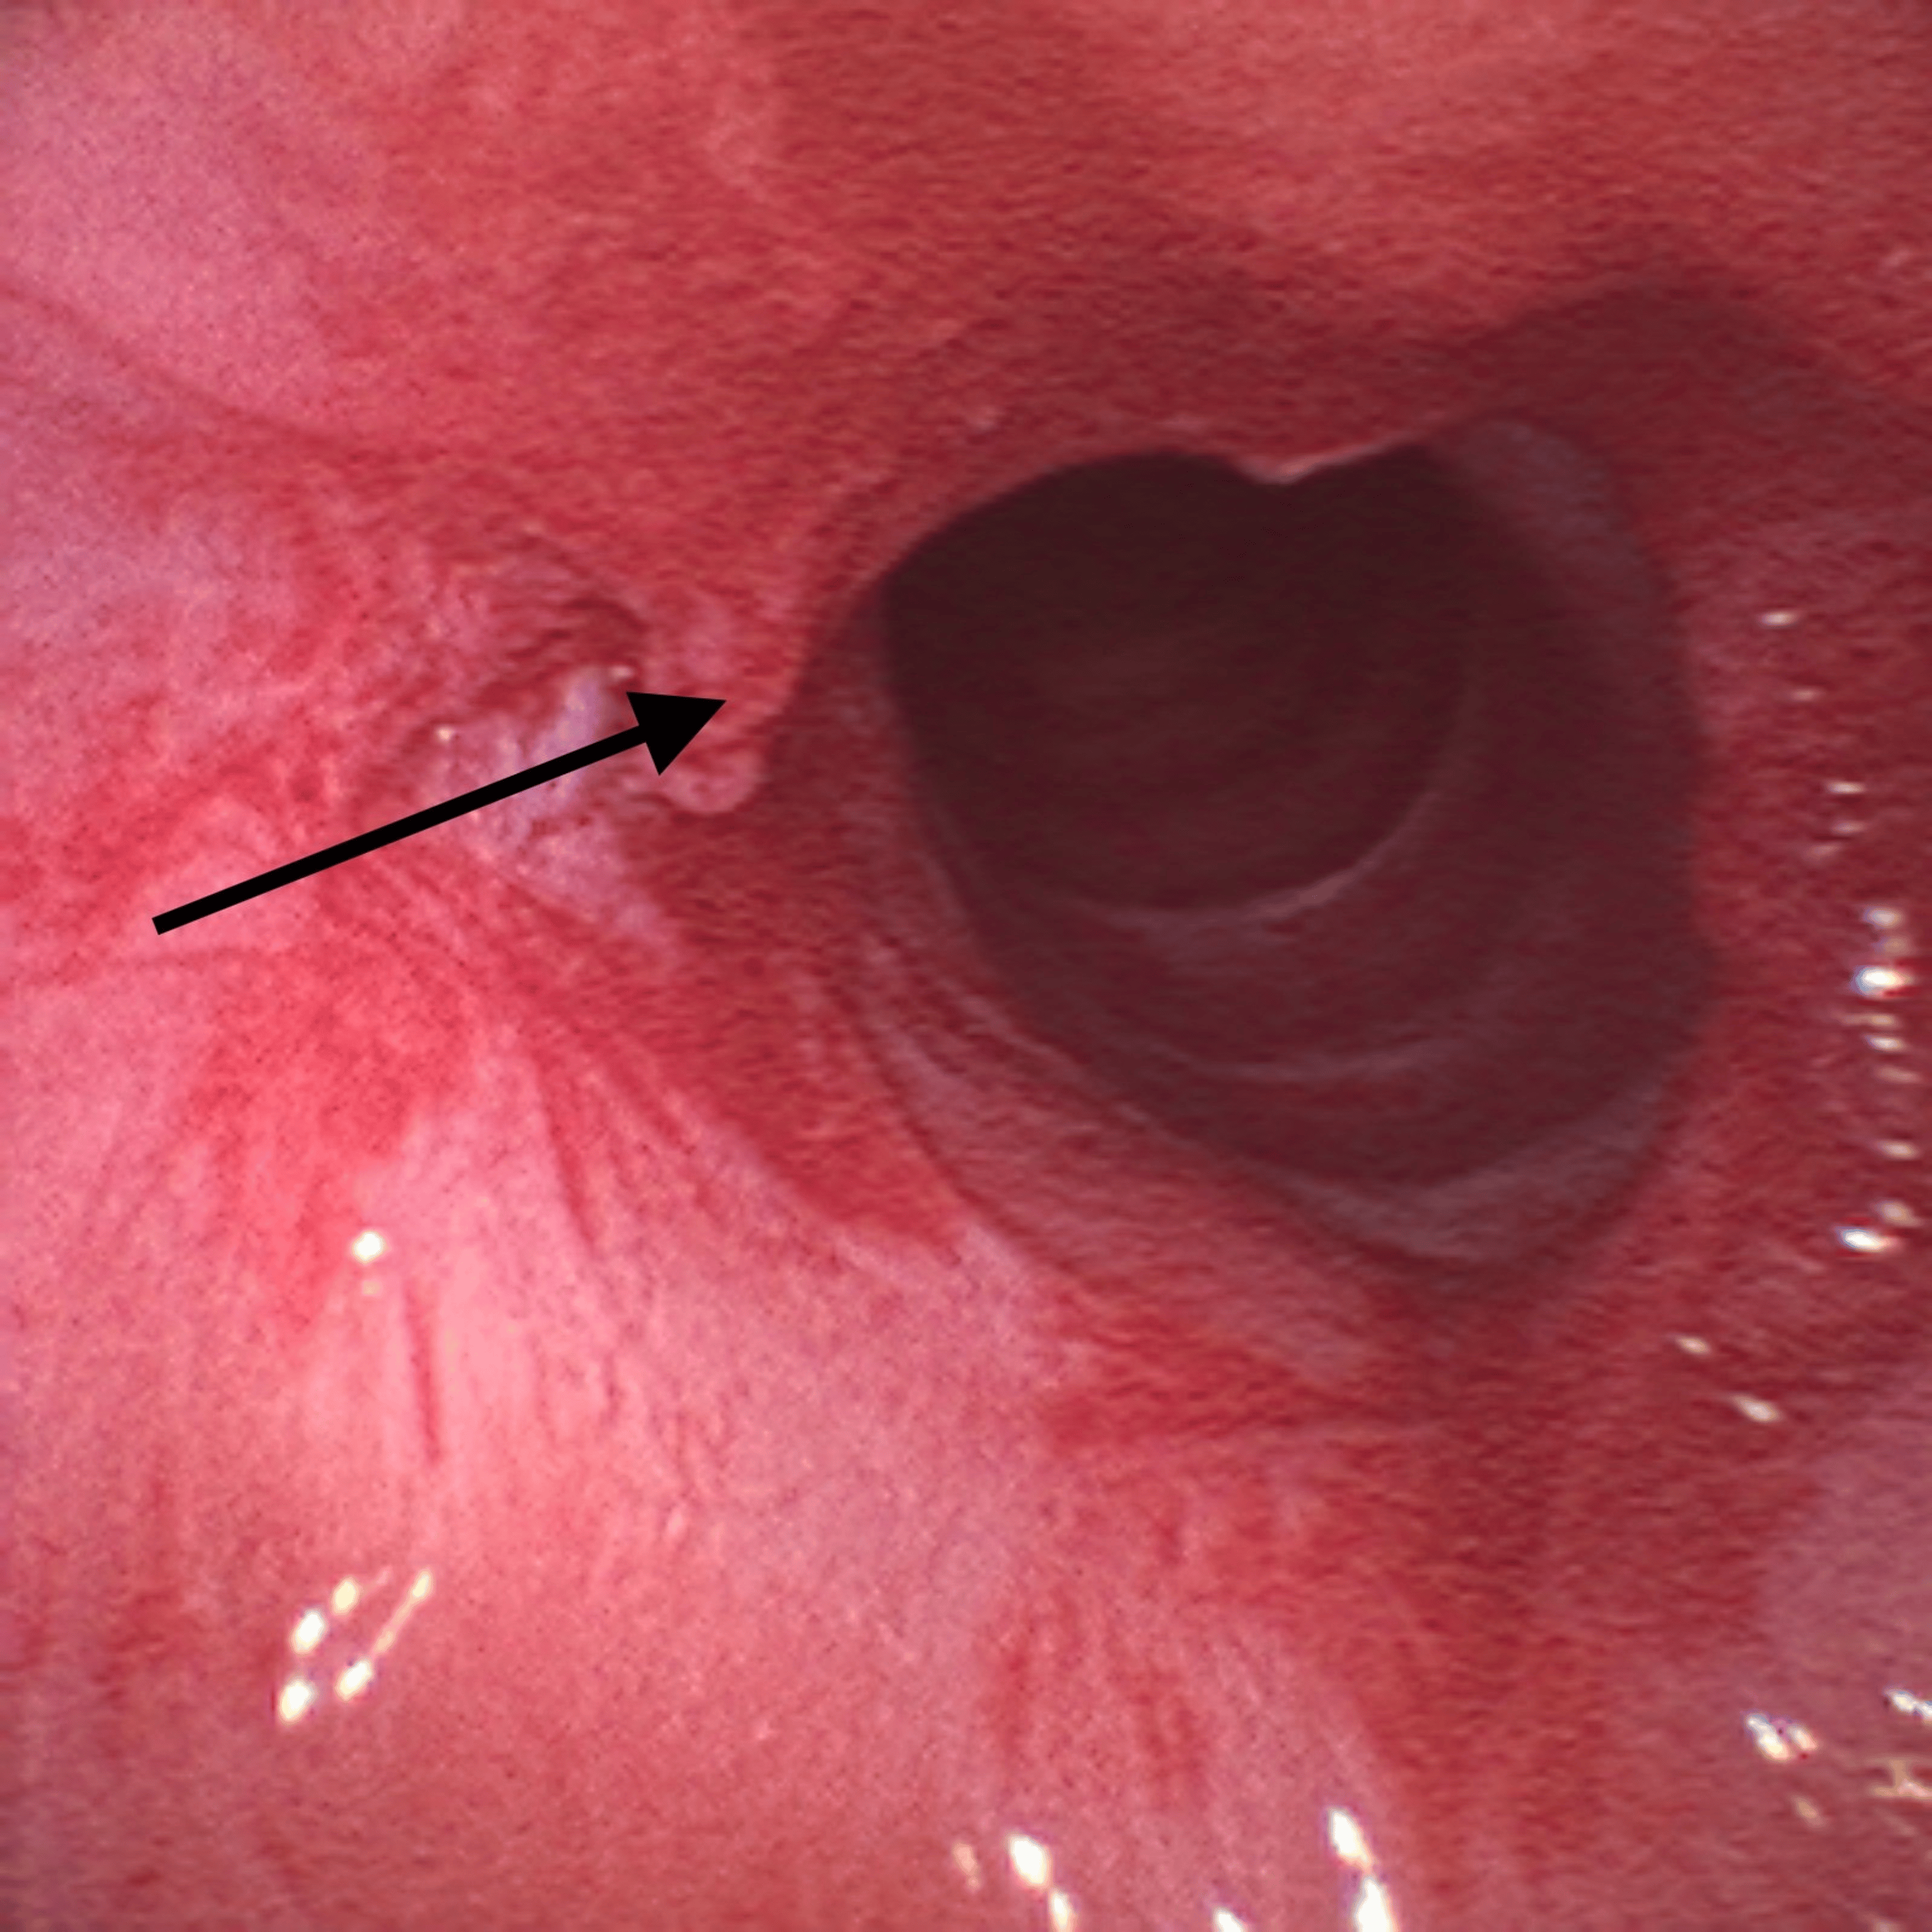

On the surgery day, a reassessment of his airway management plan was performed by a multidisciplinary team including anesthesiologists and otorhinolaryngologists. It was decided to make an asleep fiberoptic visualization of the lesion through a supraglottic device. After adequate pre-oxygenation, endovenous induction was performed using a target-controlled infusion (TCI) of propofol, Schneider model with target effect-site concentration of 4 µg/mL, and of remifentanil, Minto model. A dose of 60 mg of rocuronium was administered and a supraglottic device, AuraGain® size number four was introduced without trauma. Total intravenous anesthesia was maintained using the referred TCI. While maintaining volume-controlled ventilation with a maximum inspiratory pressure of 20 cmH2O, an Ambu® aScope™ 4 Broncho Slim 3.8/1.2 (Ambu A/S, Ballerup, Denmark) was introduced through the laryngeal mask and a circumferential fibrous membrane just below vocal cords was observed (Figure 2).

Given the findings, the supraglottic device was removed and the patient was placed in suspension laryngoscopy. Supraglottic manual jet ventilation was applied using a narrow-bore, noncompliant cannula attached to the rigid bronchoscope at one of the accessory ports on the head of the instrument. A maximum tracheal pressure of 35 cmH2O and a jet frequency of 10 per minute allowing adequate time for exhalation via passive recoil of the lung and chest wall preventing air trapping and barotrauma were applied. It was also performed with careful observation of the patient’s chest movements to ensure adequate tidal volumes without overdistension. Balloon dilatation with the application of mitomycin C was the elected otorhinolaryngologic technique (Figure 3) and at the end of the procedure, only a minimal portion of the membrane was noticed (Figure 4).